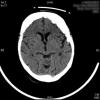

AVC amplio de territorio de A. cerebral media